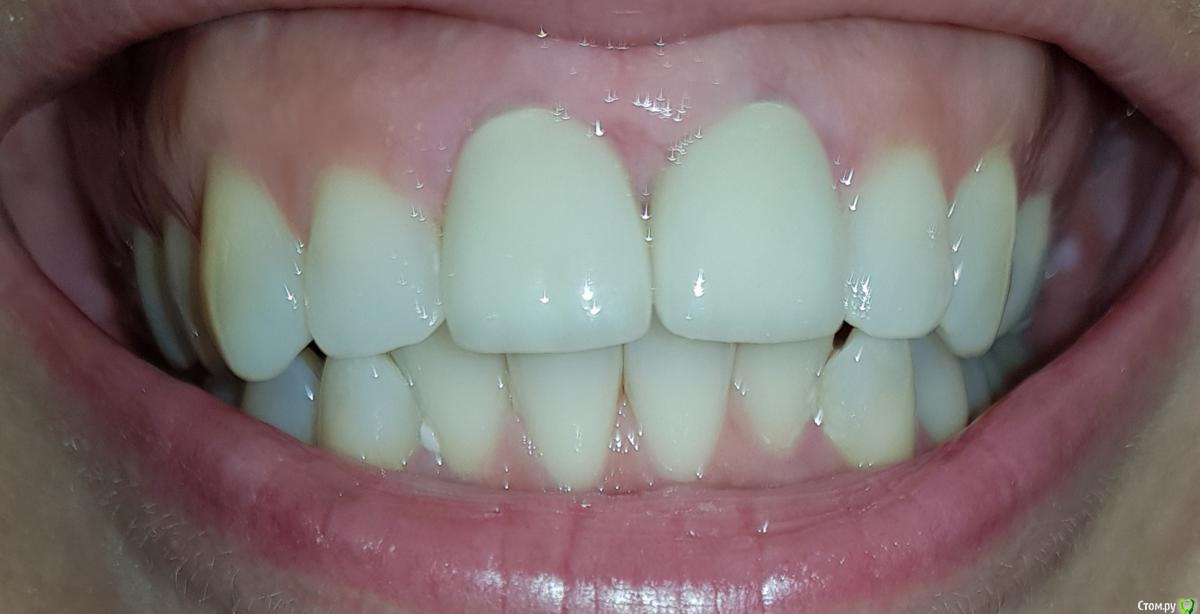

esmeron79 Опубликовано 24 декабря, 2018 Поделиться Опубликовано 24 декабря, 2018 Посоветуйте что делать. Сделали 2 передних циркониевых зуба и пришеечная окантовка оголилась. Почему шейки оголились? Когда врач мерила колпачки, они какие-то оказались большие, но виду не подала. Техник сделал на то что есть. Сосочки воспалены, сзади вообще мешается центральный, набух. Пошла к другому врачу, много счистил цемента, "сосочки" как будто сели, но центральный сзади опять набухает и передние шейки все таки оголены. От чего это могло пройзойти, может большие зубы слишком? Ссылка на комментарий